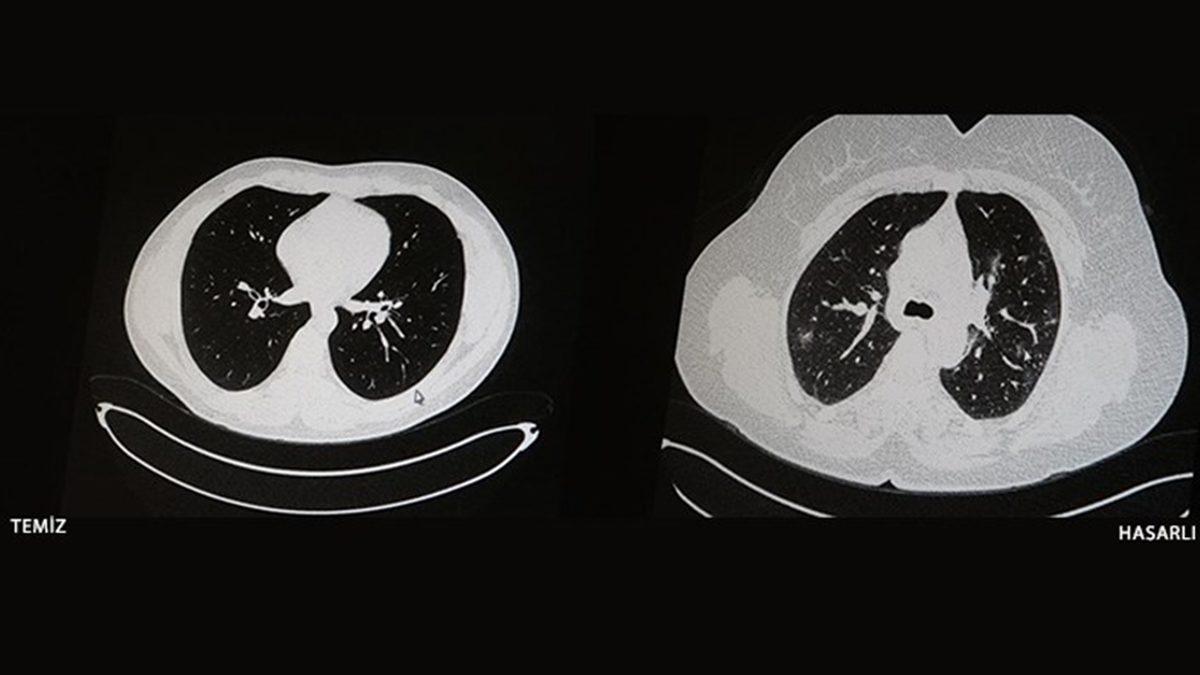

Çocuklarda ve gençlerde de etkileri sert olabiliyor. Aşısız ve aşılı iki gencin tomografileri arasındaki fark: